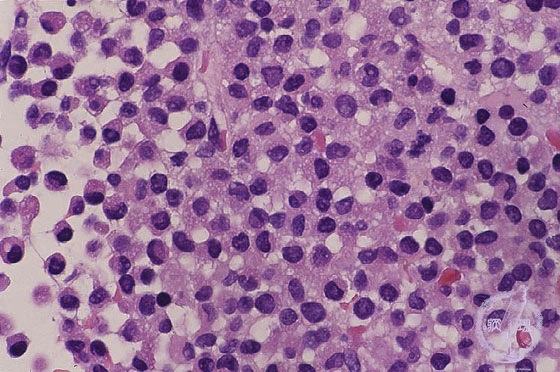

- š(5) Acute myeloid leukemia(M3)

Microscopic image (H&E high power view): Acute promyelocytic leukemia (M3). Diffuse proliferation of myeloblasts is found. This type of leukemia sometimes form green nodules, therefore it was called as gchloromah. Notoriously, it often causes disseminated intravascular coagulation (DIC).